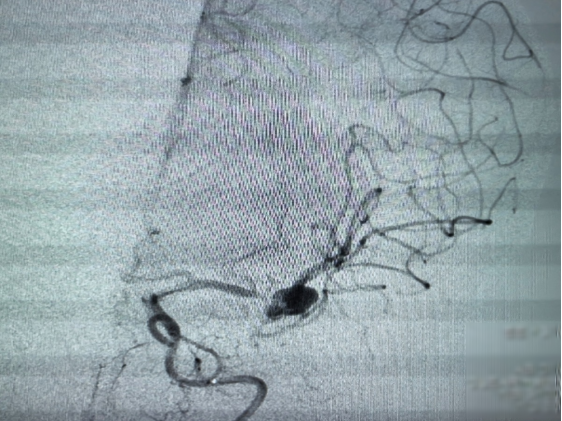

脑组织氧饱和度监测仪联合术中造影提示脑血管狭窄,有局部脑组织缺血缺氧的可能。陈文斗教授团队立即决定使用支架覆盖血管狭窄部位,后复查造影见狭窄部位较前改善,动脉瘤少许显影,无射血征,余血管显影良好。予以患者替罗非班抗凝后,脑氧恢复术前状态。

(造影提示:动脉瘤少许显影,无射血征,余血管显影良好)

手术过程顺利,术后予扩容、抗血管痉挛及抗血小板聚集等对症处理后。左脑脑氧值进一步上升,达到左右脑一致,患者安全返回病房,并经过医护团队精心护理后顺利出院。

(术后造影提示:可见脑血管支架影,脑组织供血良好